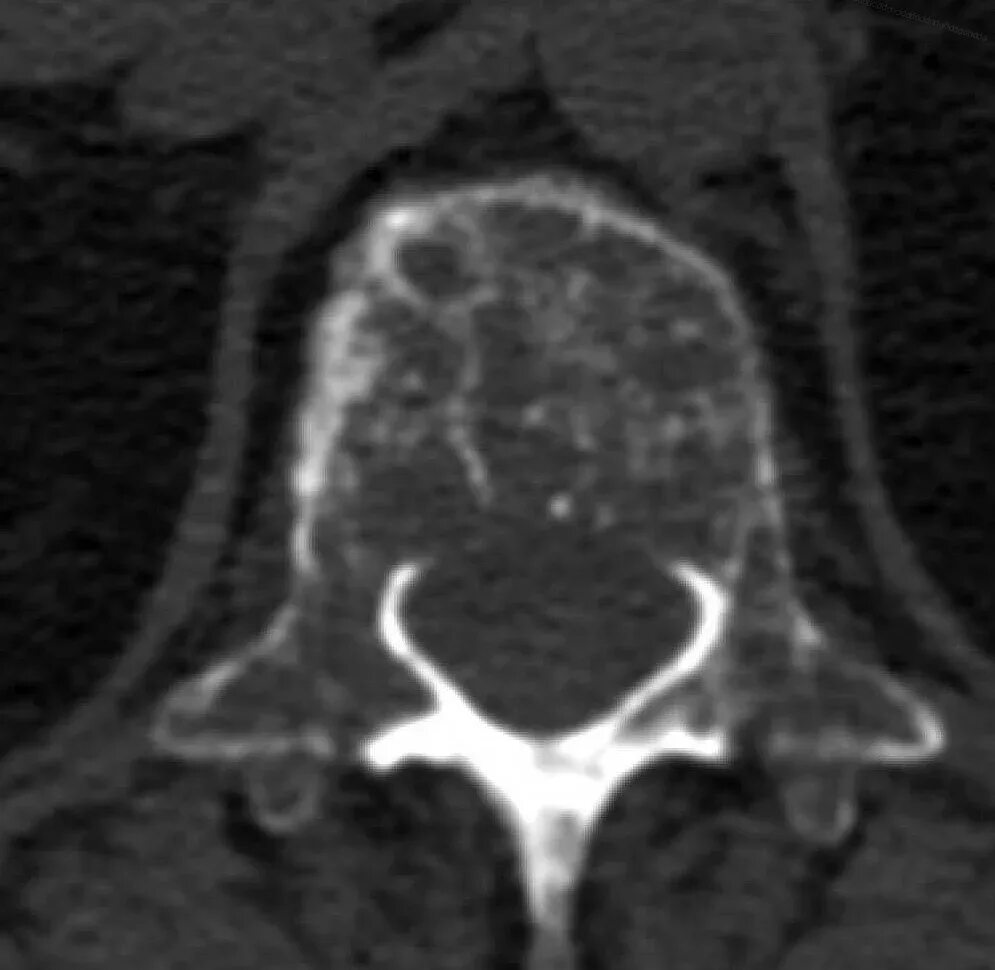

Заболевание кт